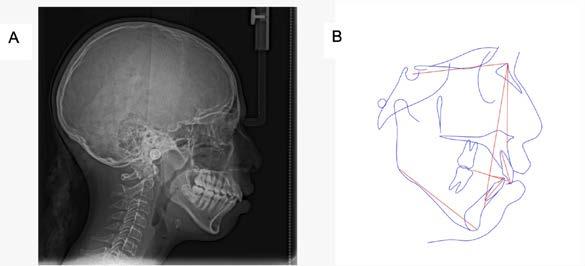

Introducción: La maloclusión clase II provoca proporciones irregulares en el perfil facial. Puede deberse a un maxilar adelantado y a incisivos superiores proinclinados y protruidos. Esta condición puede corregirse mediante el uso de aparatos ortopédicos en pacientes en crecimiento.

Objetivos: Conseguir clase I canina, controlar el crecimiento vertical, disminuir la convexidad esqueletal, reducir la sobremordida horizontal y mejorar el perfil facial. Caso clínico: Paciente femenina de 9 años, clase II esqueletal, biotipo dolicofacial, perfil convexo, clase II molar, clase II canina y proinclinación de incisivos superiores e inferiores. Resultados: Se logró clase I canina, se controló el crecimiento vertical, se redujo la convexidad esqueletal, se mejoró la sobremordida horizontal y el perfil facial. Conclusiones: El uso combinado de aparatos ortopédicos y aparatología fija en pacientes en crecimiento, junto con un diagnóstico y plan de tratamiento acertado, permite obtener resultados exitosos y estables en la corrección de estas maloclusiones.

La relación maxilomandibular desempeña un papel importante en la posición de los molares y puede clasificarse como clase I, II o III, de acuerdo con la clasificación de Angle. Esqueletalmente, esta relación solo puede determinarse mediante estudios radiológicos; los modelos de estudio solo ofrecen una aproximación clínica.1